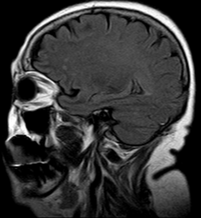

El conocimiento de las entidades mas frecuentes en la rama de neurología permitirá al médico de primer contacto, identificar las alteraciones por las cuales acuden a un servicio de urgencias o inclusive al servicio de consulta externa. El reconocimiento, la identificación, el tratamiento inicial o en su defecto el envio al servicio correspondiente, permitirá al paciente disminuir considerablemente el índice de morbimortalidad.